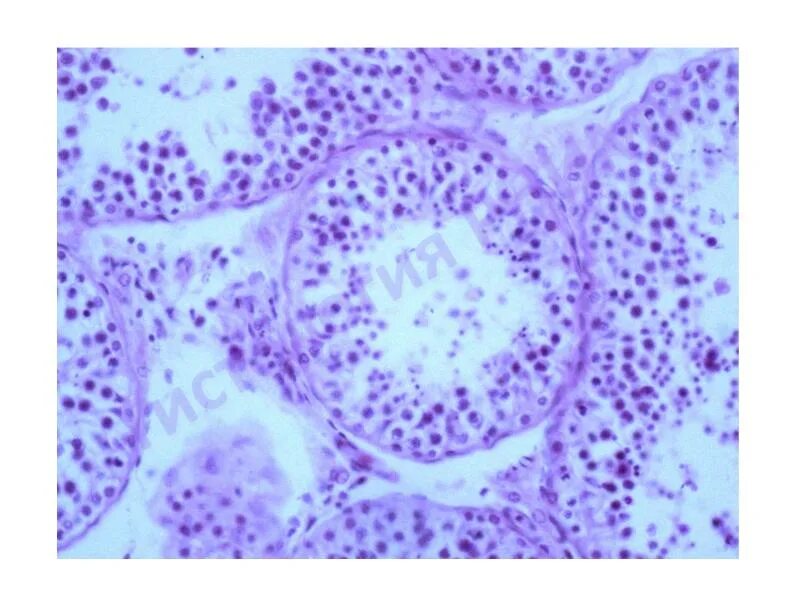

Общая эмбриология гистология